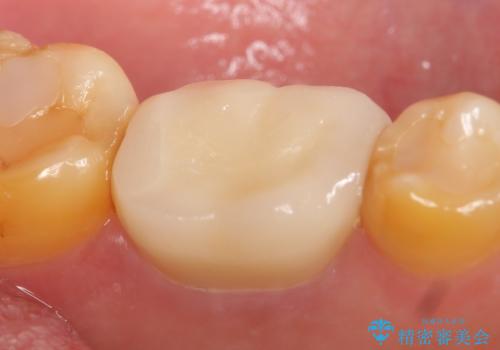

咬合痛等の症状の緩解、根尖病変の縮小傾向、および深かったポケットが正常値まで改善したことを確認後、オールセラミッククラウンによる補綴を行いました。

オールセラミッククラウンの色に関しては、患者様の希望により他歯より白い色で製作しました。

今回用いたオールセラミッククラウンはジルコニアフレームという白い素材の上にセラミックを盛っているため、審美性が非常に高いのが特徴です。

また、ジルコニアは人工ダイヤモンドの材料にも使われているほど高い強度を持っており、そのためオールセラミッククラウンは審美性だけでなく、奥歯やブリッジの補綴も可能とするクラウンです。